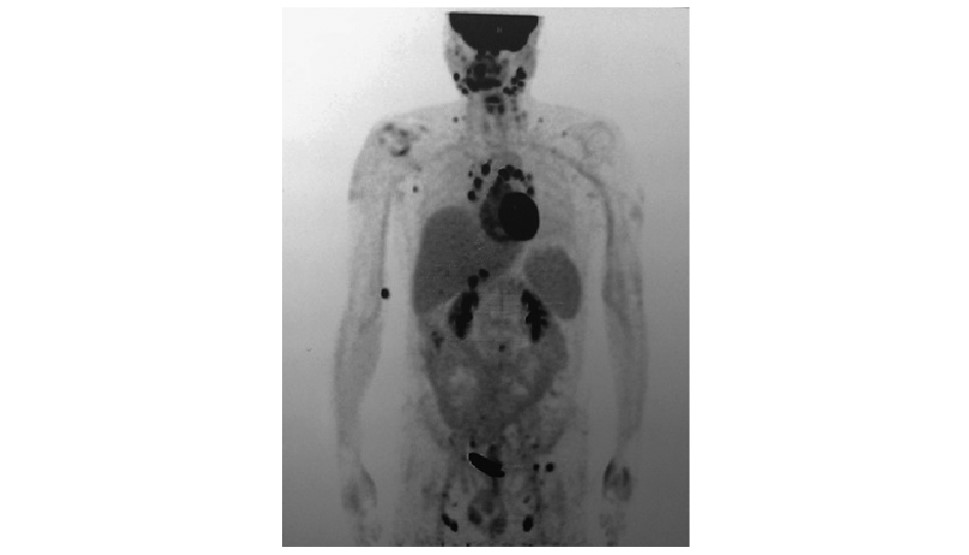

• 摘要: 建立正确的临床思维是提升临床能力的核心和根本,是医学教育的重点及难点。与常见病不同,垂体疾病作为一种罕见病,其临床思维具有其独特性。本文以一例下丘脑垂体多发占位为例,从资料搜集、逻辑推理、循证教学、多科讨论、基础医学研究等方面总结罕见病诊断思维特点,以期提高临床医师的工作效率,并为垂体疾病的临床思维训练提供相关经验。

Abstract: Establishing correct clinical thinking is the core and foundation of improving doctors' clinical ability as well as the key and difficult point of medical education. Different from common diseases, clinical thinking about pituitary diseases has its unique characteristics as a rare disease. Taking a case of Hypothalamic and pituitary mass as an example, this paper summarized the characteristics of diagnosis thinking of rare diseases from the aspects of data collection, logical reasoning, evidence-based teaching, multiple disciplinary teams, and basic medical research, to improve the efficiency of physicians and provide experience for the training of clinical thinking about pituitary diseases.